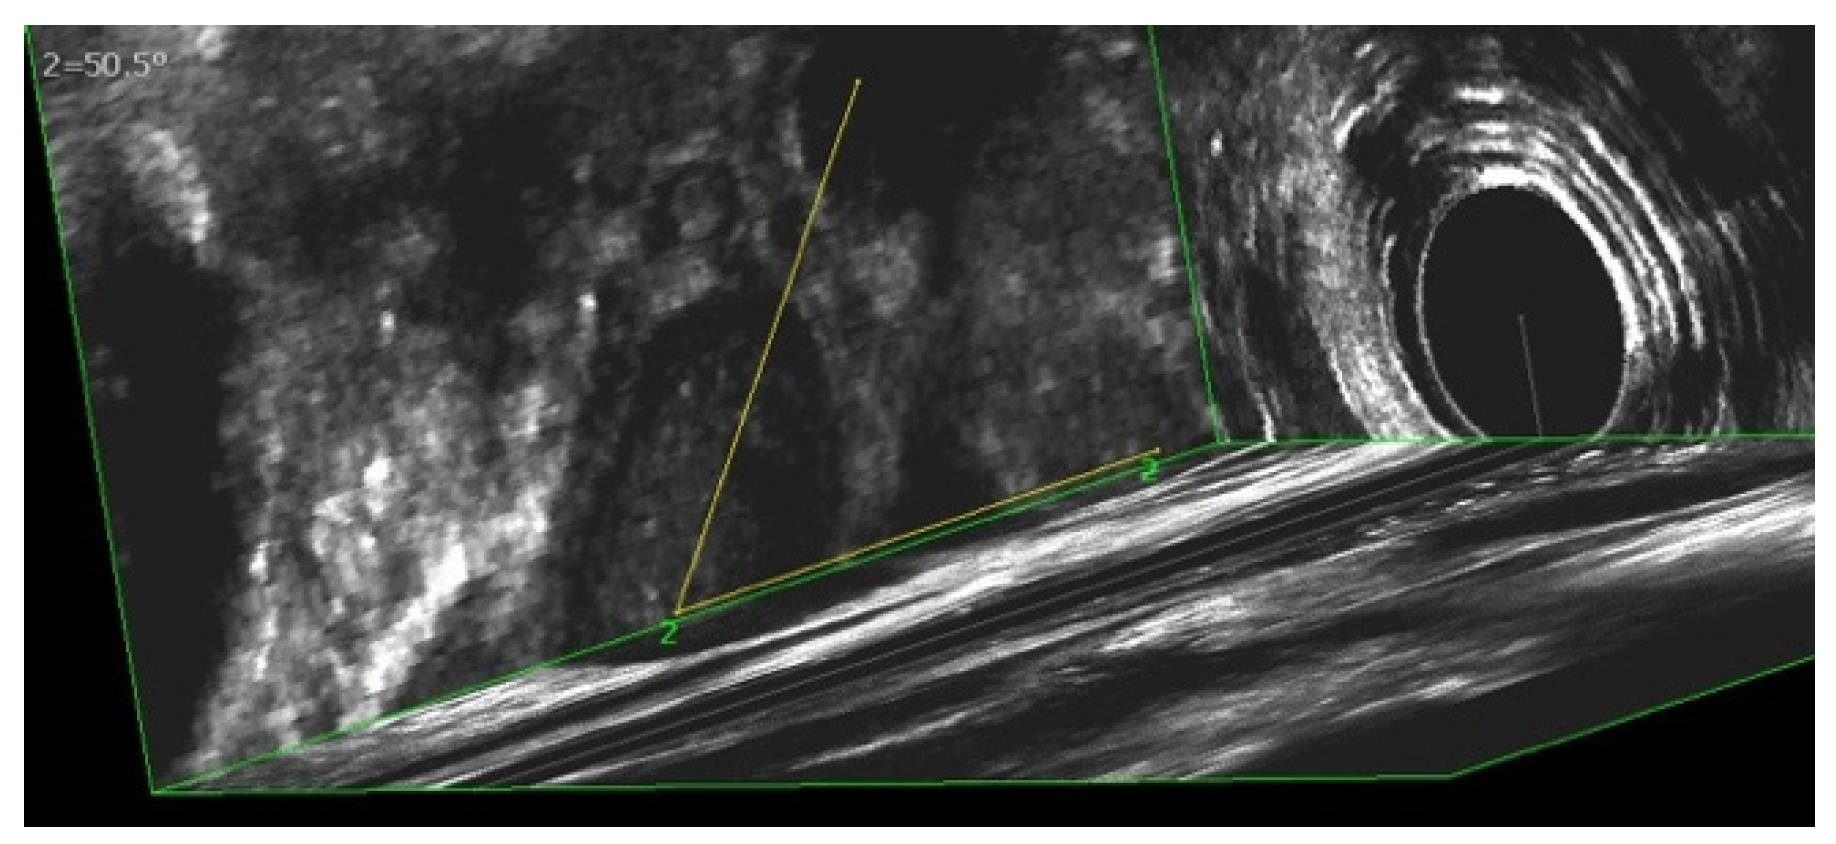

3.4. Evaluation of Sphinkeeper Implants

| EAUS—internal sphincter defect [grade], median (range) | 67.5 (38–121) |